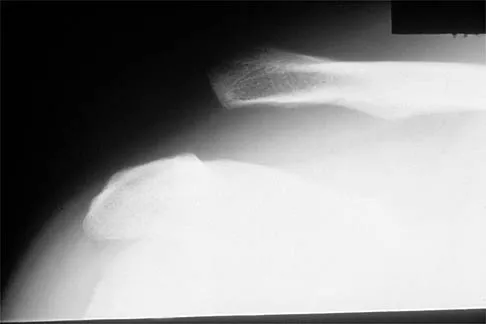

Question 74

Figure 17 shows the radiograph of a 25-year-old professional football player who has superior shoulder pain that prevents him from sports participation. History reveals that he sustained a shoulder injury that was treated with closed reduction and temporary pinning 3 years ago. The best course of action should be

Explanation